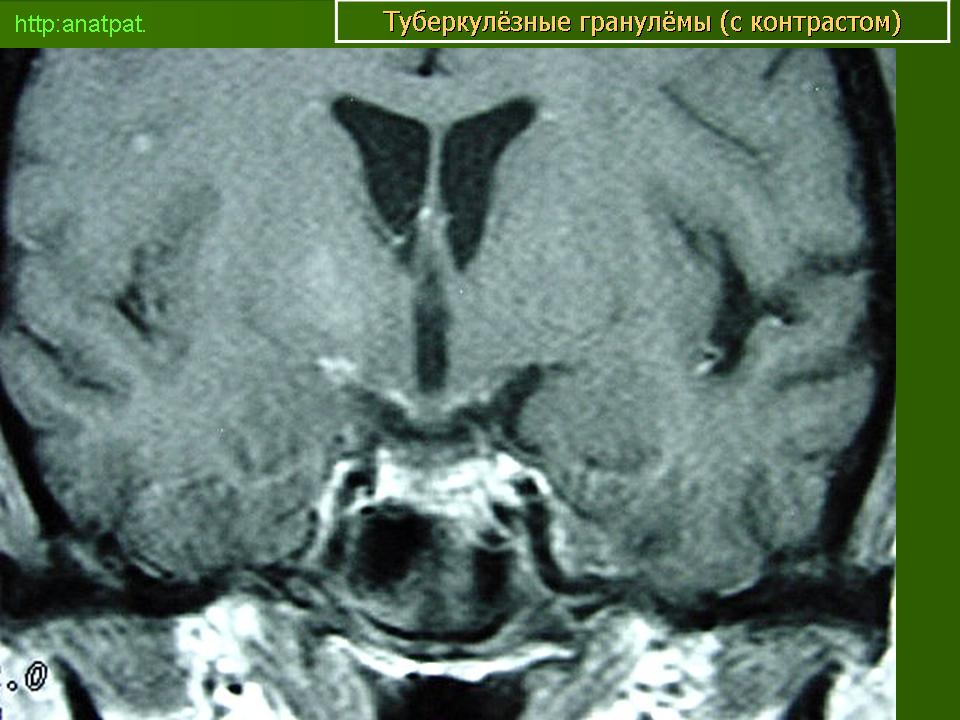

Менингеальный больной туберкулёзом на фоне ВИЧ.

anatpat.unicamp

Приложения:

131129-1.jpg131129-2.jpg131129-3.jpg131129-4.jpg131129-5.jpg131129-6.jpg131129-7.jpg131129-8.jpg131129-9.jpg131129-12.jpg131129-13.jpg131129-14.jpg131129-15.jpg131129-16.jpg131129-17.jpg131129-18.jpg131129-19.jpg131129-20.jpg131129-21.jpg131129-22.jpg131129-23.jpg131129-24.jpg